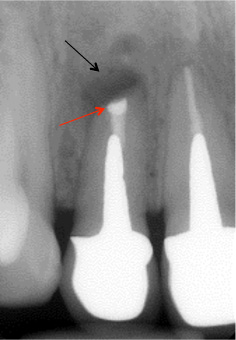

白丸で囲んだ部分が原因であるにも関わらず、レントゲンでは異常をきたす所見はありません。

CTで見たときも悪い黒い影は見当たりません。黄色の矢印は骨です。しかし、赤の矢印の部分の根の先端は骨から少し出てるような感じがします。

これだけでは、確定的な診断は出来ませんが、「フェネストレーション」の疑いはかなり高いです。